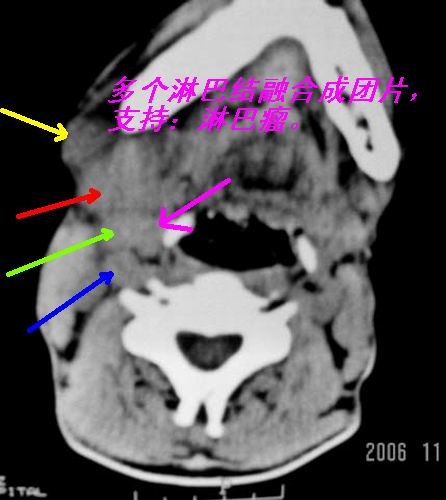

以下是引用zjzjr在2006-11-28 23:07:00的发言:[br]右侧颌下及右侧胸锁乳突肌内侧可见多个肿大淋巴结影,边界欠清,密度不均,最大者中央部见液化坏死区,具有融合趋势。考虑淋巴瘤。